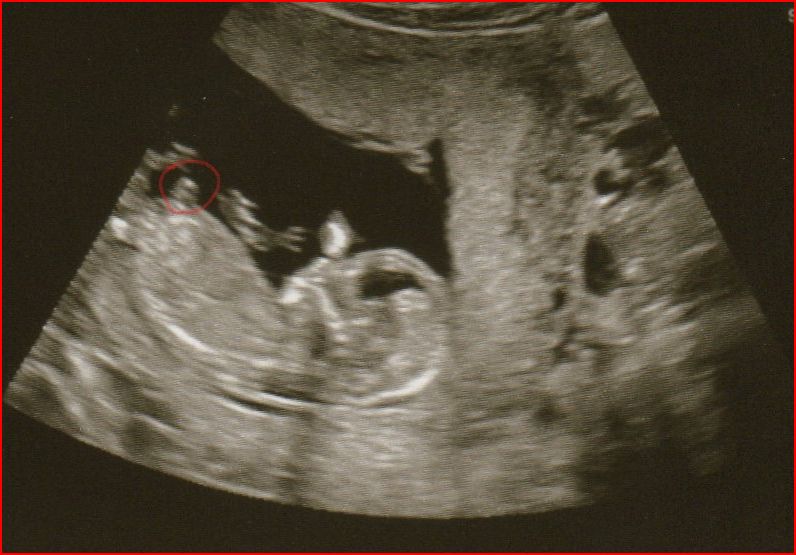

I'm certainly no expert, but I'm *feeling* like the third photo may show a flat nub...so I'll guess girl. Cute little baby! :)

Never mind hope you don't mind but i worked out how to do it. Thinking that may be a nub and it look pretty flat at that gestation. Have uploaded the pic on this post in case it helps you get more guesses.

Ok hope you don't mind but i blew the others up to, whilst i was sticking my nose in, just in case it helps you get any more guesses :happy:

girl.

Thinking Girl..good luck!